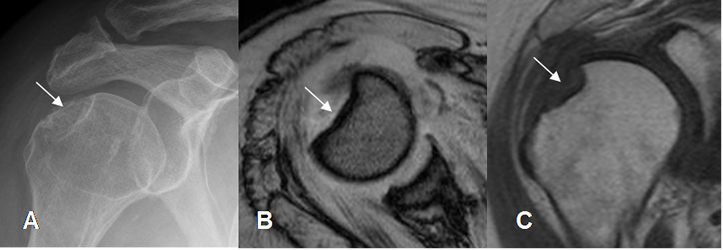

Fig 49. Fractura de Hill Sachs.

A: Rx AP, B: RM axial en FFE y C: RM coronal en T1. Zona deprimida en la parte superoexterna de la cabeza del húmero, por fractura de Hill Sachs.